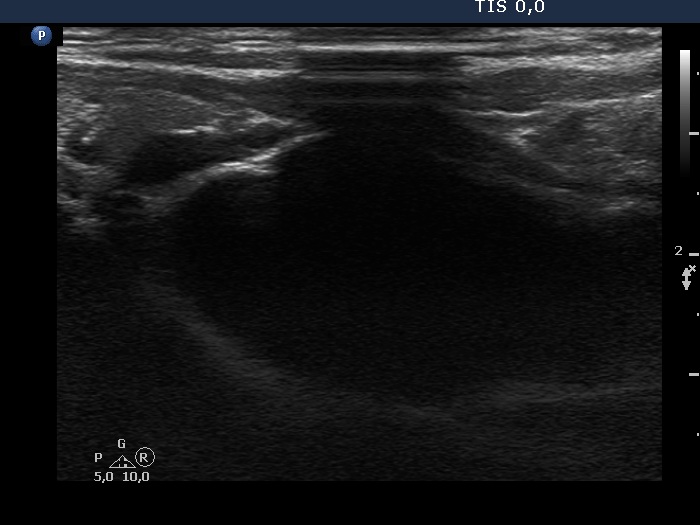

Parathyroid lesions - case 97 (ultrasonographic picture 8)

Under the left lobe, longitudinal view. In this section, the ultrasound probe could not be fit properly which caused an acoustic shadow.